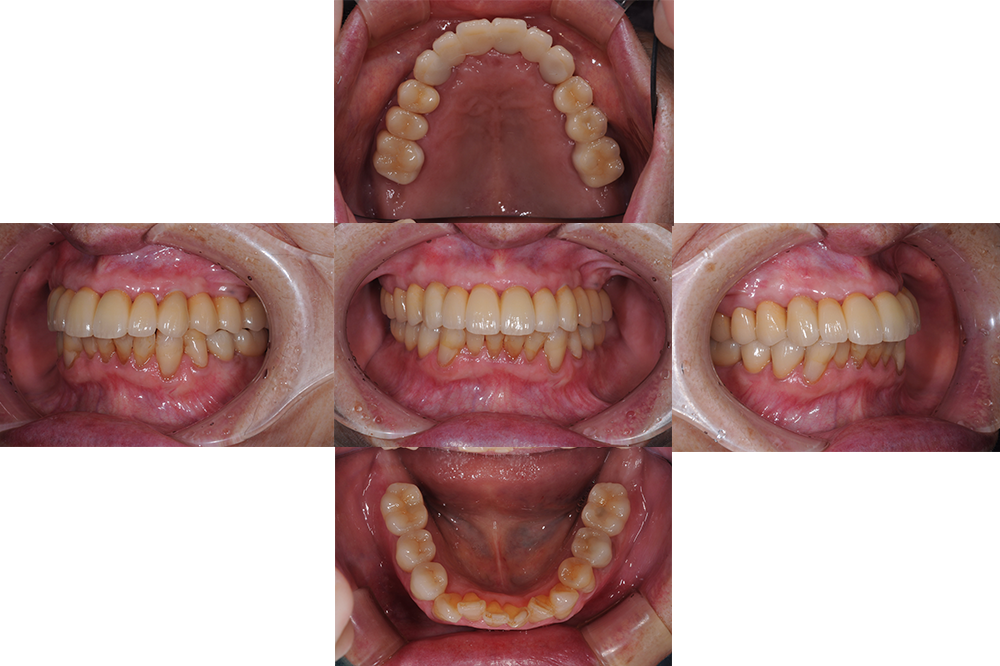

奥歯が外れた(80代)インプラント・セラミック修復

年齢 80歳

性別 女性

初診日 2019年 1月

主訴 奥歯が外れた

治療内容 ・インプラント

・セラミック修復

治療期間 1年3ヶ月

治療費用 550万円

治療経過 高齢ではあったが、入れ歯はどうしてもいれたくないということでインプラントを選択。

上顎は長期的な予後が見込める歯が少なく多数のインプラントを必要としたが、一時的にも義歯を使うことなく、咬める場所を温存しながらインプラントへと移行できた。

初診時不安定だった咬み合わせもスムーズに行えるようになり、不安なく食事ができるお口の状態を獲得できた。